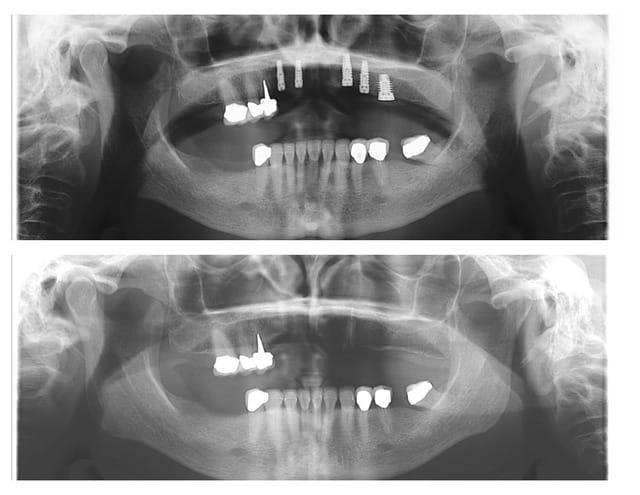

Tient, pour toi, petit montage photos, du cas de ce matin.

1er cas d'expansion fait suite formation Sallanches.

C'est pas un gros cas complexe, mais juste assez difficile, et juste assez cool pour moi.

Patiente adressée suite à une ré-hab prothétique fait en 2010, perte de la canine 6 mois après...donc stellite plutôt mobile, comme la 14 et bientôt la 37, mais bon, on commence le projet implanto.

Exo de la 23 + implantation immédiate

Expansion kit Meissegner et lame 15

Pose de 2 implants (13 et 11)

Pose 22 impossible, j'ai tenté, mais crak, bof, j'ai placé en 24 et 25.

Un peu de granules osseuse (23)

Les photos sont de ma nouvelle 2e assistant implanto.